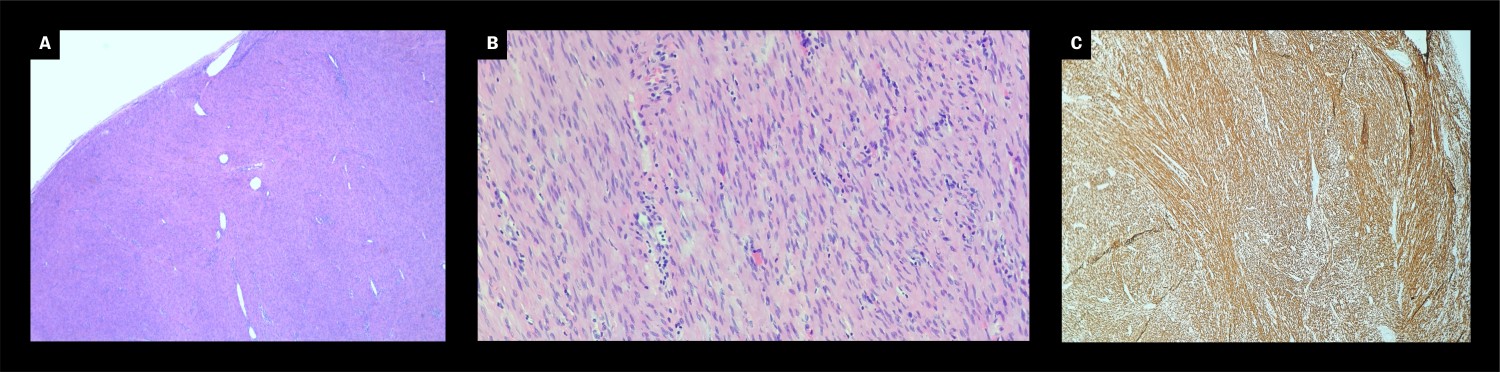

Macroscopic examination showed a well-defined, smooth-surfaced nodule measuring 5 × 4 × 2 cm and weighing 23 g. Figure 1 shows the greyish-white solid cross-sectional surface seen on dissection of the tumour. Microscopic examination revealed fascicles of spindle-shaped cells with eosinophilic cytoplasma and elongated nuclei without prominent nucleoli (Figures 2a and 2b). There was little mitosis, and necrosis was not detected. This was consistent with a benign tumour. Immunohistochemically, the tumour cells were homogeneously positive for desmin (Figure 2c) and to a lesser degree for DOG-1, consistent with smooth muscle differentiation. There was low proliferation (Ki-67 < 5 %). SOX10, S-100, CD117 and CD34 were negative in the tumour tissue. This result ruled out a tumour with neurogenic differentiation (for example schwannoma) or a gastrointestinal stromal tumour (GIST) outside the gastrointestinal tract, which were considered histological differential diagnoses. The nodule was surrounded by scant collagen fibre with capsule-like appearance. This finding confirmed the clinical assessment that the tumour had been removed in its entirety.